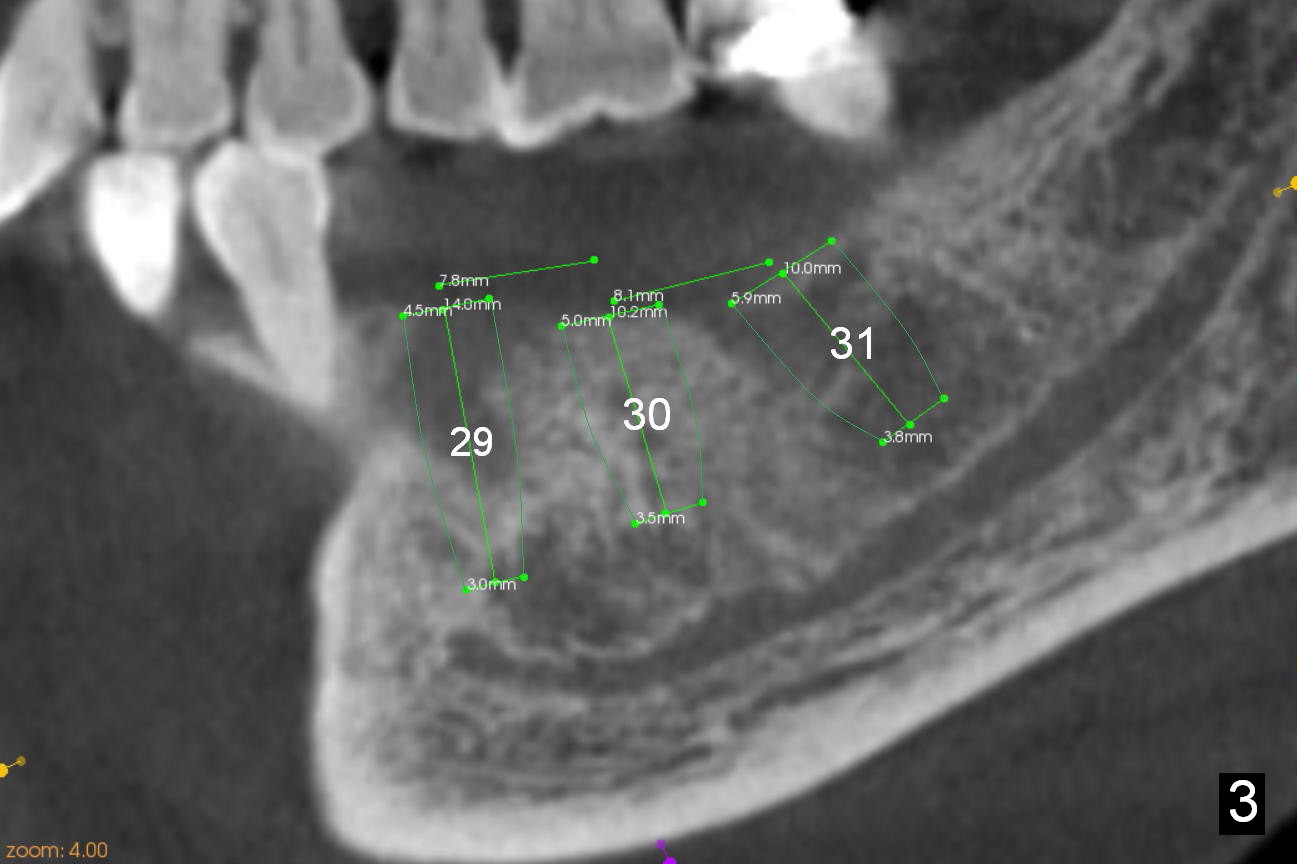

Chief complaint of a 69-year-old lady is "I cannot eat after bottom right bridge removal" (Fig.1). Exam reveals that the tooth #15 is also missing (Fig.2). Four implants are planned. CBCT shows low density of #31 socket (Fig.3,4, bone expanders) and the buccal coronal portion of the #29 socket (Fig.3,6,7, place implant as lingual as possible). The alveolus at the site of #30 is atrophic coronally (Fig.5). If insertion torque of individual implants is reasonably high, an immediate provisional bridge will be fabricated.